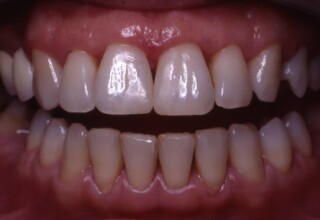

Restoration of bilateral diastemas between central and lateral incisors.

Diastemas were created mainly because of narrow laterals. After orthodontic treatment was finalized, the diastemas were closed with two composite resin restorations.